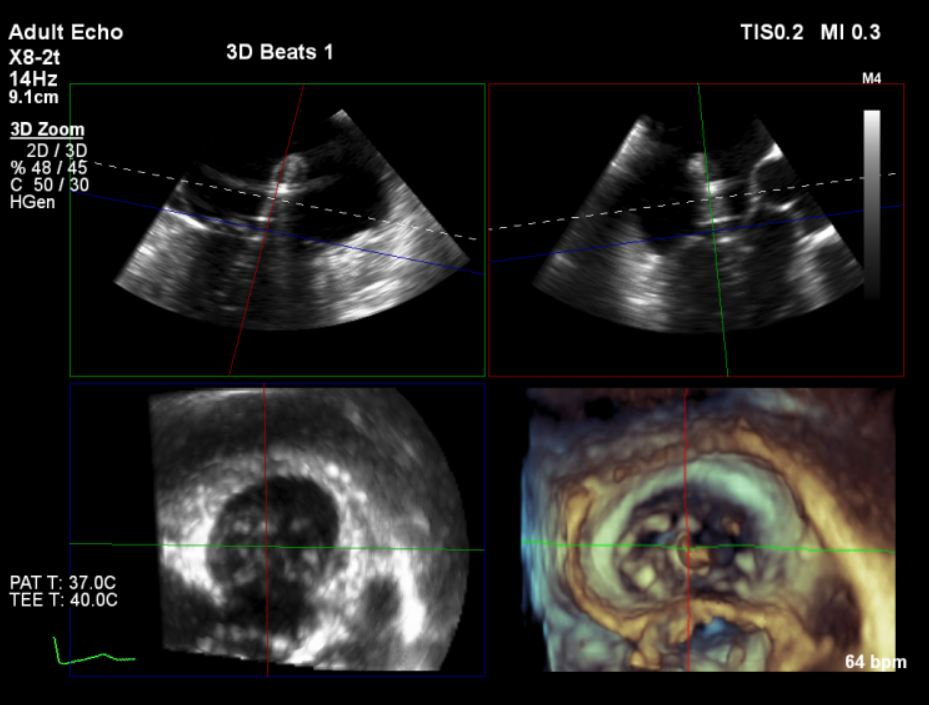

经过云南阜外医院结构性心脏病MDT团队综合讨论评估该患者病情后,患者为传统手术高危患者,瓣膜病变解剖无法行介入修复,决定进行MitraFix™经心尖二尖瓣植入。术前心脏CTA二尖瓣D形瓣环面积折算直径34mm, 模拟植入34号介入二尖瓣膜(外经约40mm)后左心室NeoLOVT面积可(>150mm2)。手术在单纯超声引导下完成,采用左侧肋间4cm微创切口心尖入路,在超声引导下,输送系统准确跨瓣,并将瓣膜准确释放于二尖瓣瓣瓣环,瓣膜释放后支架贴合牢固,无瓣周漏及瓣内反流,二尖瓣前向血流通畅,平均压力阶差2mmHg,左心室流出道通畅,流出到血流速度为2.3m/s,平均压力阶差8mmHg(图2-3,视频1)。顺利撤出输送系统,关闭心尖切口,手术顺利结束。

图3:采用3D实施多平面定位引导瓣膜释放